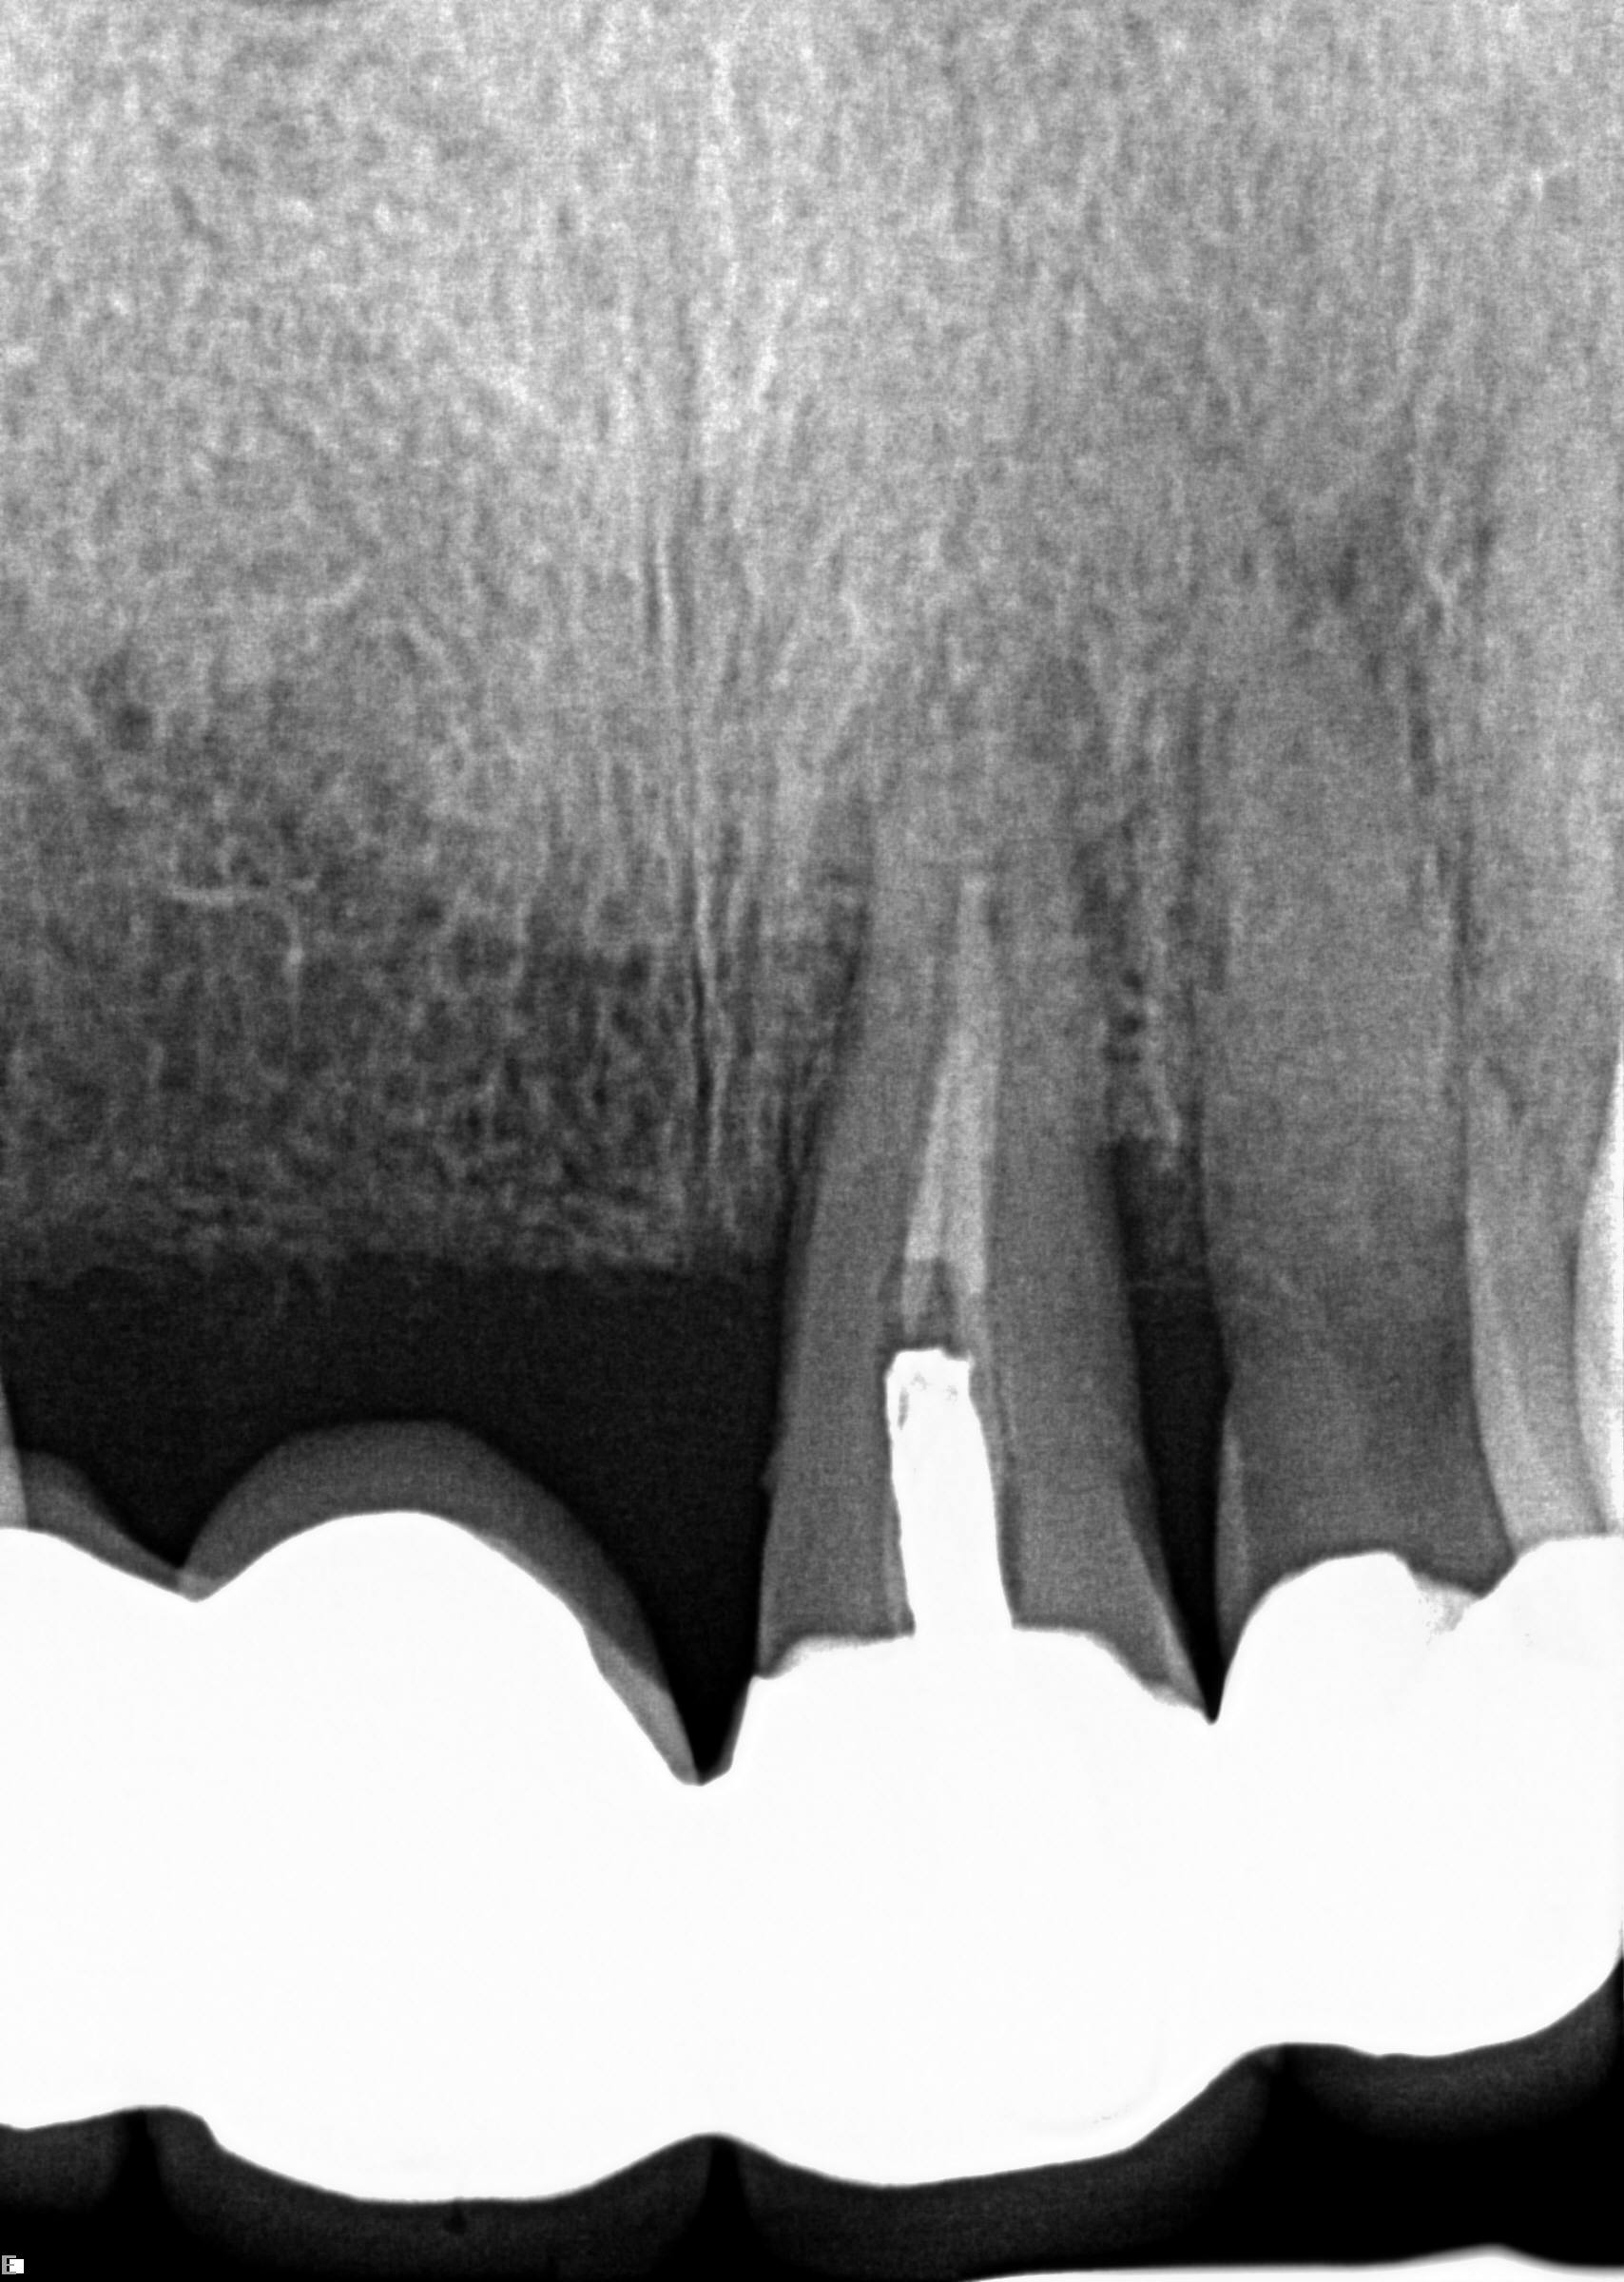

A 42-year-old man presented with a very loose bridge on Nos. 6 through 9 with periodontally compromised retainers on Nos. 6 and 9 (Figure 17 through Figure 19), and endodontically involved No. 10 with a calcified canal. Teeth Nos. 6, 9, and 10 were extracted, the sockets fully debrided, and pontic soft tissue on Nos. 7 and 8 sculpted to be symmetrical in soft tissue contour with the contralateral lateral incisor and central incisor locations. Implants were secured in position Nos. 6 through 10 (Figure 20) in excess of 45 Ncm, the bone was milled to provide unimpeded seating of temporary abutments, and temporary crowns were fabricated chairside and adjusted to be out of occlusion in centric relation and all excursions. The temporary crowns were cemented after extrusion of excess cement extraorally and the patient was prescribed antibiotics, analgesics, and instructed in postoperative care particular to immediately provisionally restored implants. At 6 months, integration was confirmed (Figure 20 through Figure 23) and after placement of scanning abutments, the implants and soft tissues were scanned. Final crowns were fabricated from the scanned images and were cemented after extrusion of excess cement extraorally (Figure 24 through Figure 26), and oral hygiene procedures were reviewed.

(17.) Case 3 initial radiograph of bridge on Nos. 6 through 9 and crown on No. 10.

Figure 17

(18.) Case 3 initial radiograph of bridge on Nos. 6 through 9 and crown on No. 10.

Figure 18

(20.) 6-month integration confirmation of Nos. 6 through 10.

Figure 20

(21.) 6-month integration confirmation of Nos. 6 through 10.

Figure 21